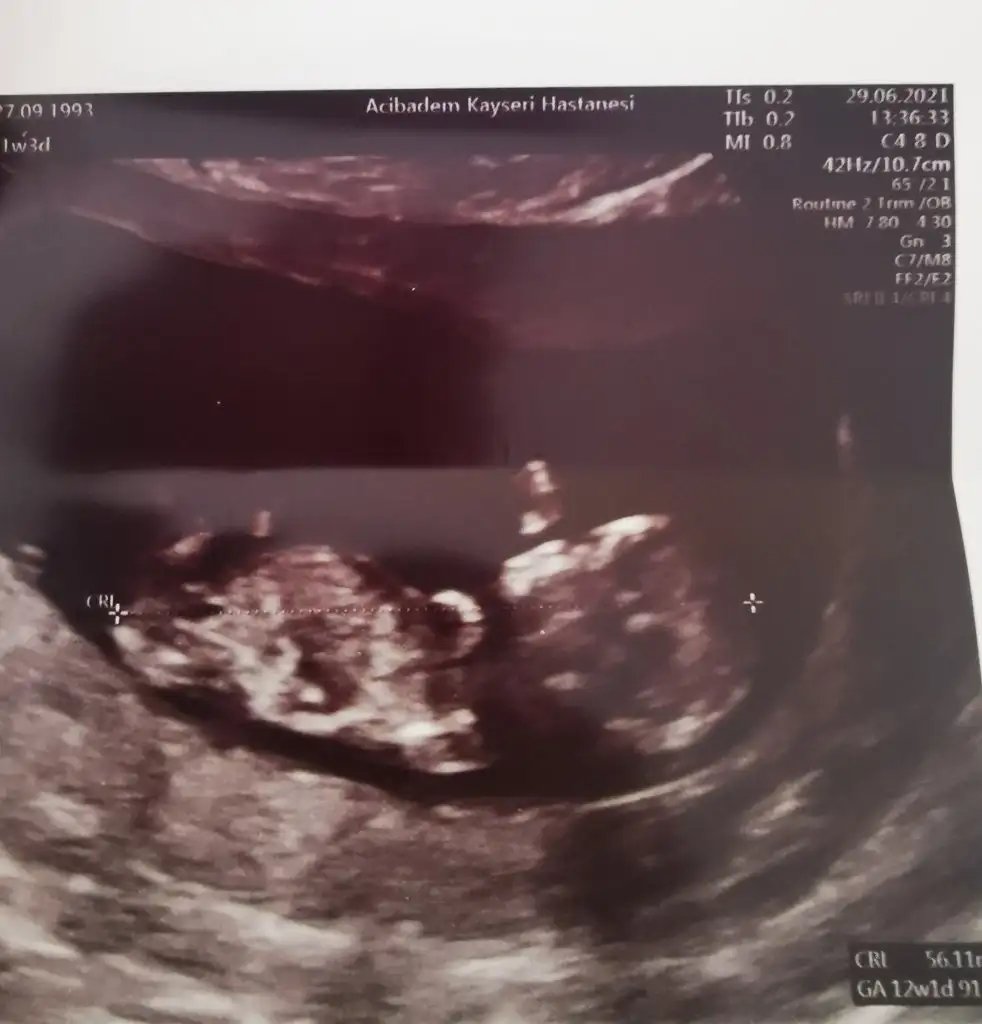

Günler o kadar yavaş geçiyor ki birde bir an önce göbeğim belli olsun istiyorum normal mi acaba bu psikoloji18.haftada öğrendim ben 12.ci haftada doktor tahminde bulundu 18.ci haftada kesinleşti bebişimiz kızhaklısınız cinsiyetini öğrenene kadar deli givi ultrasom fotoları paylasıyordum

Ben 13+2 dün %80 erkek dedi. Ama kesin değil ufaklığı görünce kesinleşirKızlar selam ben 2 ay 1 günlük hamileyim de her günüm ayrı heyecan şimdide dört gözle cinsiyeti bekliyorum sizler cinsiyeti hangi haftada öğrendiniz?

İnşallah bir sonra ki randevumda görünebilir14. Haftada büyük ihtimal kız dedi. 17. Haftada pozisyonu uygunda uzun uzun inceledik bacak arasını emin olduk. Erkekse 13. 14.haftada görünür pozisyon uygunsa.